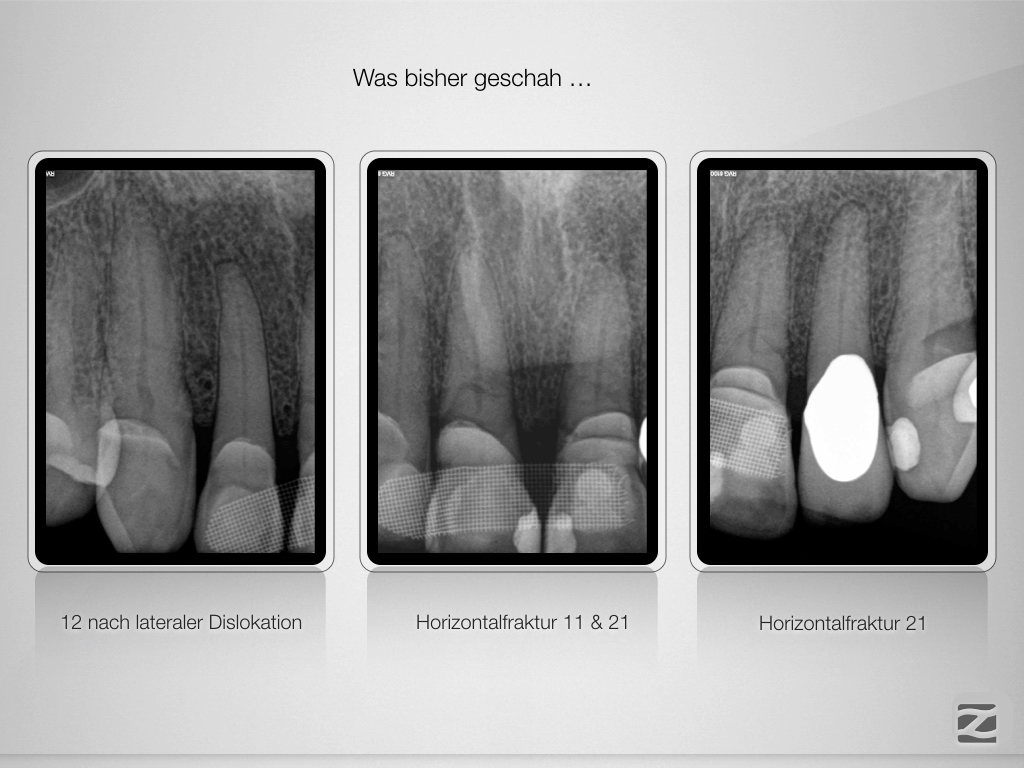

Trauma, externe Resorption & Pulpotomie